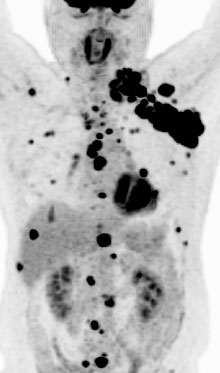

図:PET-CT 左頚部から縦隔、肝臓、骨、皮下などの多発転移性病変

特に、頭や首(頭頸部)や肺が原発のがんを見つけるのに、FDG-PET/CT検査が有用であるとわかっています。